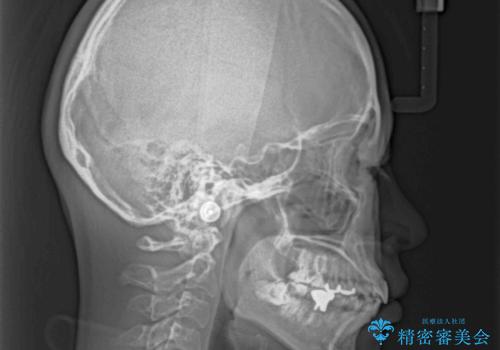

- 口元の突出感と奥歯のむし歯を気にして来院された患者様です。

奥歯の虫歯は事前に矯正治療用の仮歯に置き換えて矯正治療を行い、装置除去後にセラミッククラウンにて補綴治療を行うこととしました。

通常は上下左右の第一小臼歯4本を抜歯することになりますが、左側下顎の第二小臼歯は既に根管治療をされており、予後が良くないとのことでこの歯を抜歯し、ワイヤー装置にて矯正治療を行うこととしました。

第二小臼歯抜歯はイレギュラーな治療手段であり、治療期間が延びる傾向にありますが、予定よりも早い2年間で終えることができました。